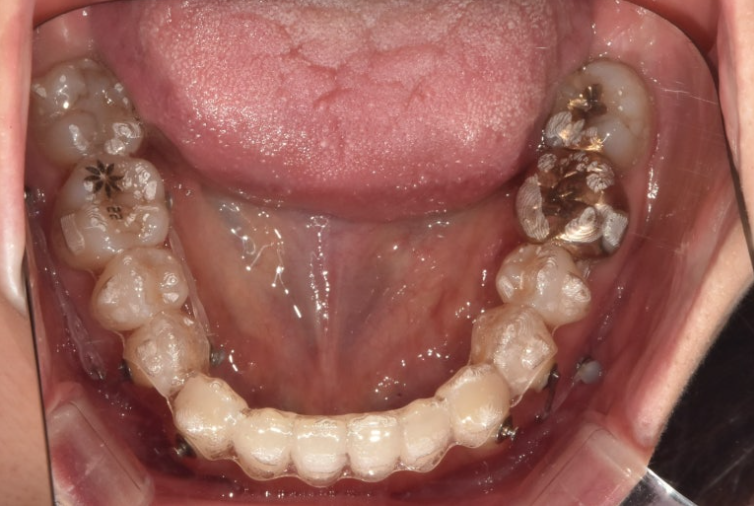

24.01

왼쪽 위 큰어금니 1개가 임플란트이며 앞니가 삐뚤삐뚤합니다.

주걱턱 부정교합은 아래 앞니를 지지하고 있는 치조골이 얇은 경우가 많습니다.

그만큼 블랙트라이앵글의 발생 위험도 높죠. 이부분을 개선하기 위한 치간삭제가 들어가겠지만 그래도 어느정도 블랙트라이앵글은 감안해야 하는 부분입니다.